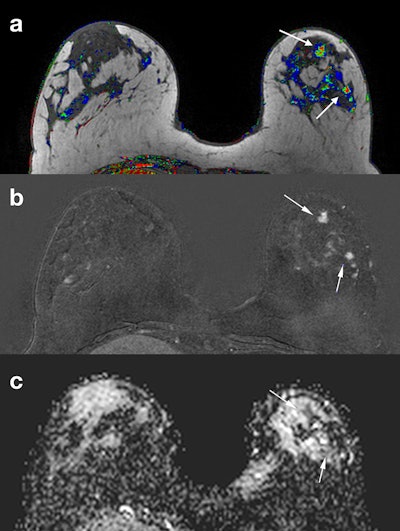

DWI provides complementary information to dynamic contrast-enhanced (DCE) MRI exams. It has already proved its value in single-center studies on lesion characterization and response evaluation but has a less clear-cut role in tumor profiling through prognostic associations. Technical issues due to standard echo-planar imaging (EPI) are gradually being solved, but the technique must be completely standardized, and clear interpretation guidelines must be issued before DWI can become fully incorporated in breast cancer diagnosis and response evaluation, she explained.

The high intrinsic contrast achieved with DWI without the injection of external agents, and the ease of implementation into multiparametric protocols due to the fact it is an inexpensive and fast sequence, has triggered several studies on the role of DWI as an alternative to DCE for breast cancer screening. This research has been undertaken in different populations, mostly in patients with suspicious mammographic and ultrasound findings. Because of the issues raised by breast density legislation in U.S., as well as concerns about the long-term use of gadolinium contrast agents, this is a very active area of research with promising preliminary data, she pointed out.

"One of the most interesting areas of research today is the evaluation of residual disease after neoadjuvant treatment," she said. "Residual disease has been traditionally evaluated with contrast-enhanced MRI, but research shows that diffusion adds sensitivity for predicting a pathologic complete response, which is the holy grail in response evaluation."

"We have to become very familiar with these new terms," she said. "Diffusion can increase the accuracy of contrast-enhanced MRI in everyday clinical practice. I use diffusion a lot when I am staging a breast cancer and I see additional lesions that I would like to characterize."